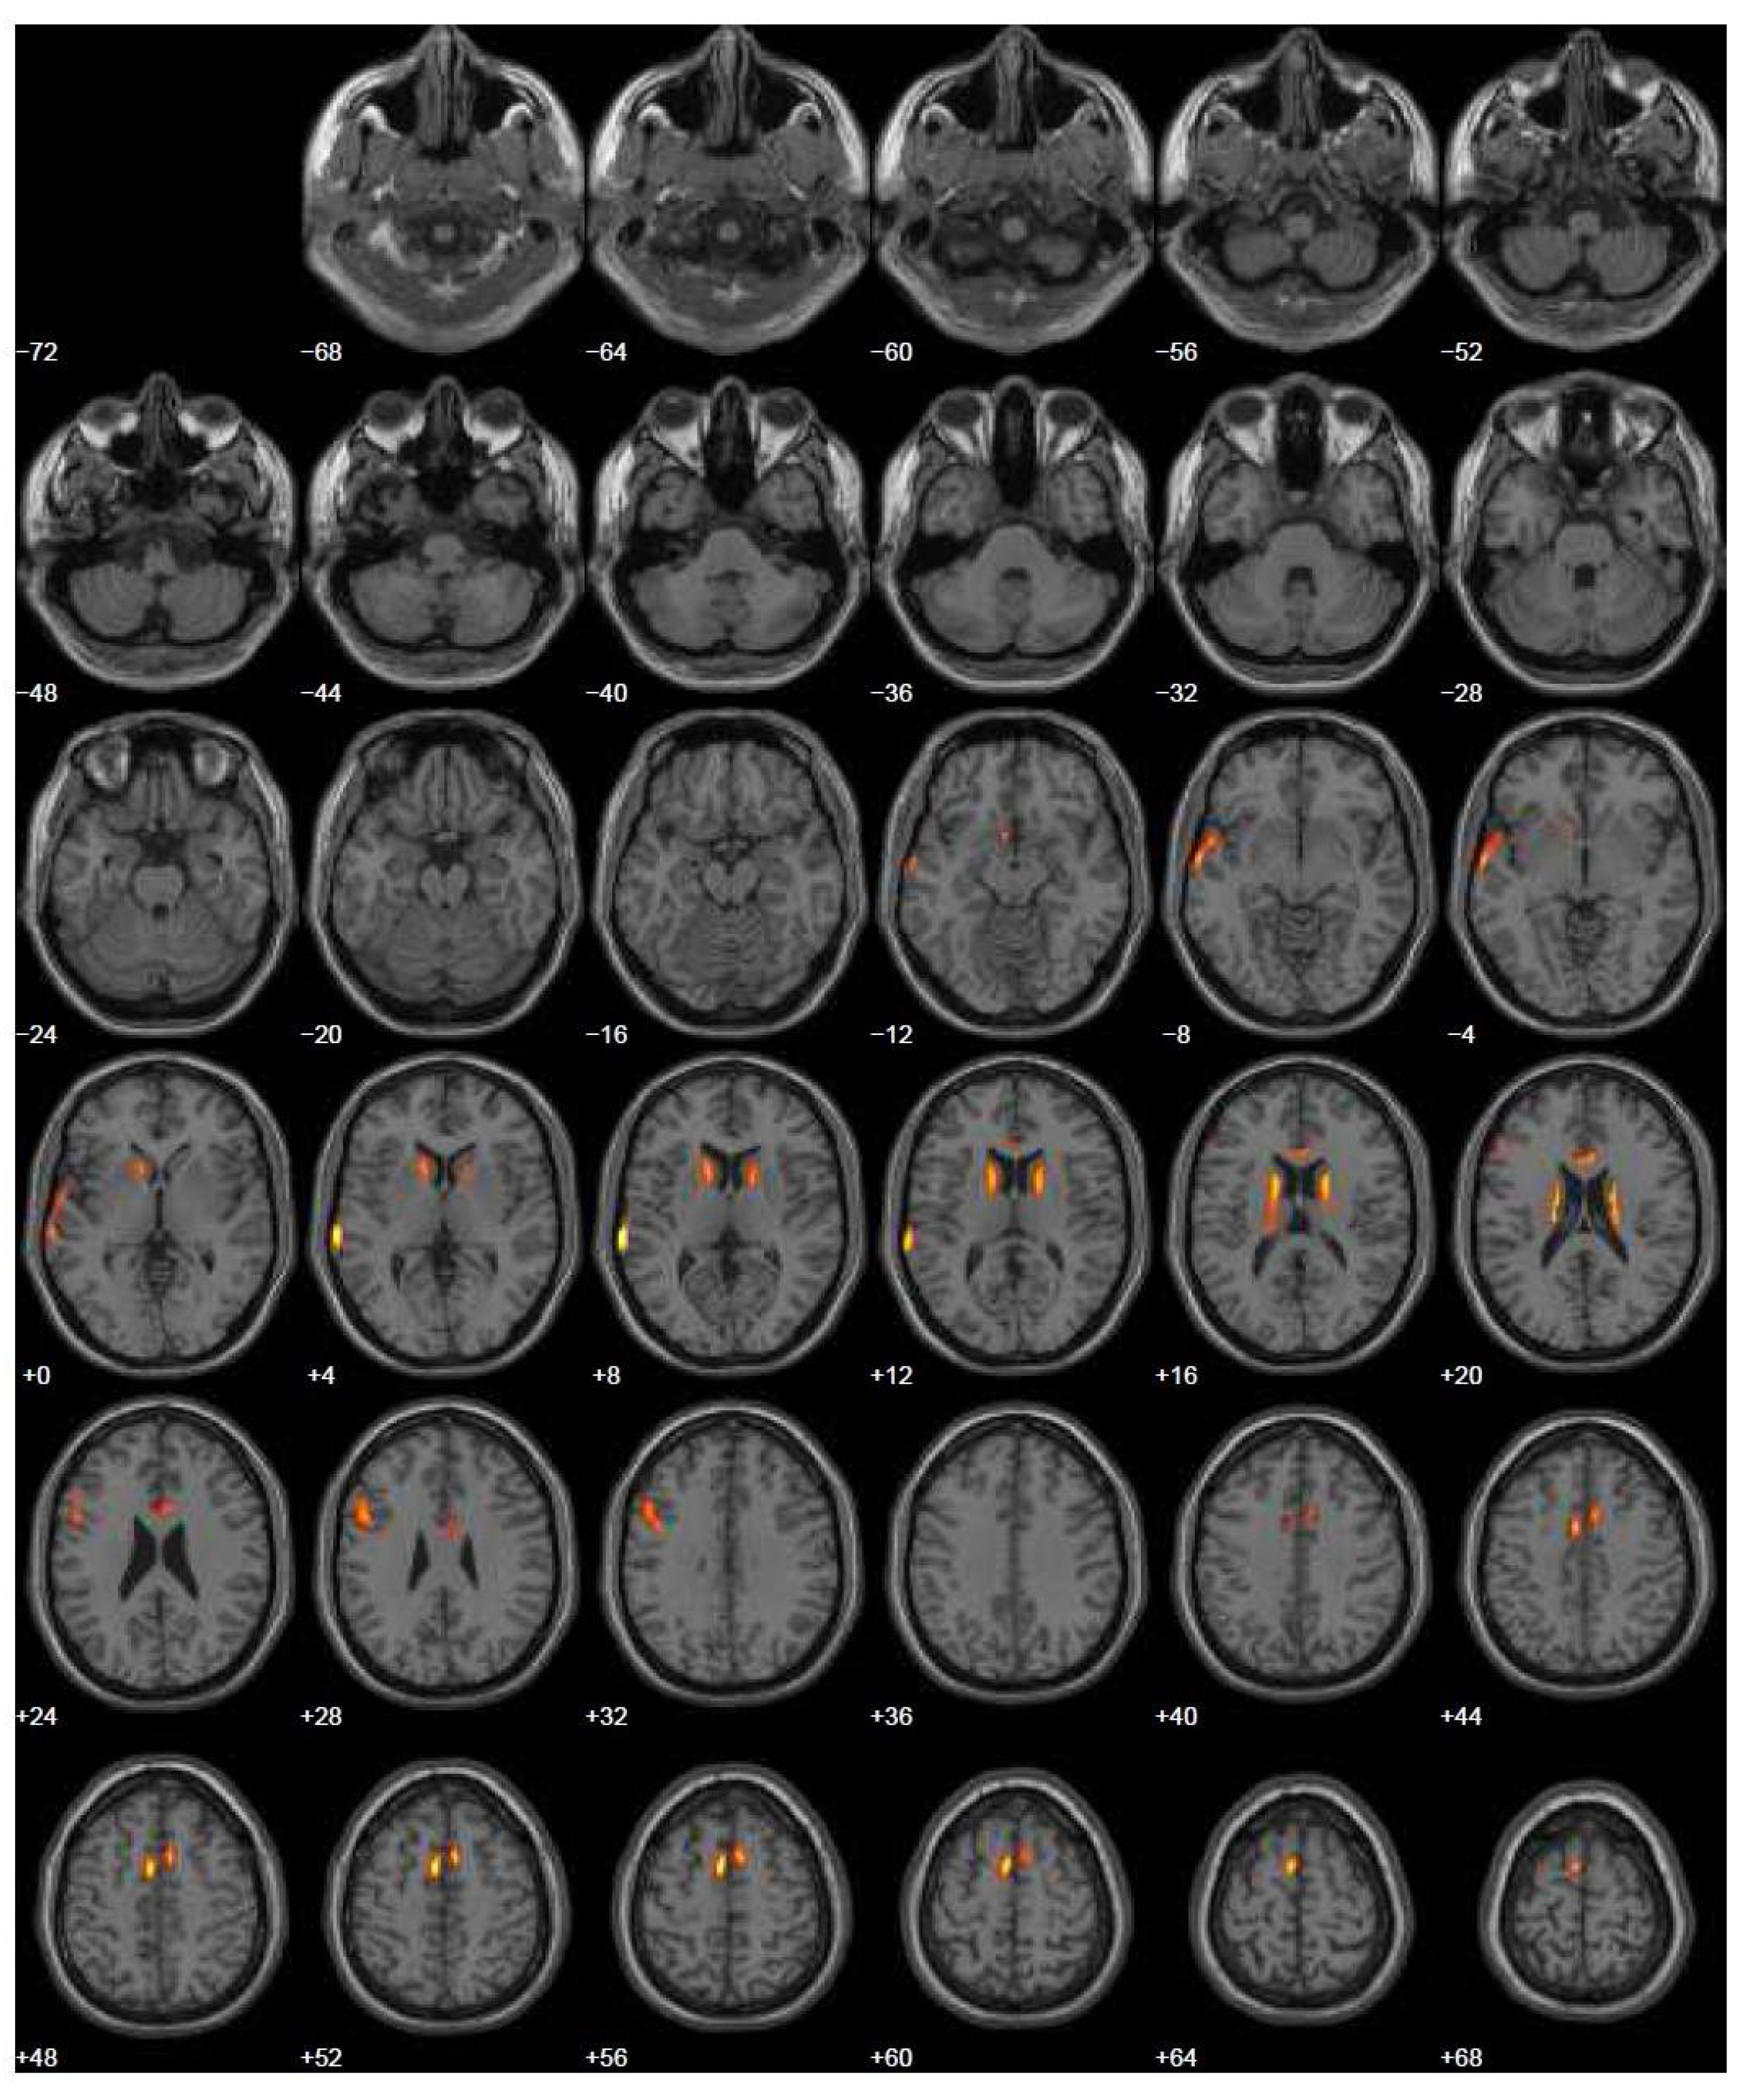

| 2013 | FDG-PET | Hypometabolism in the right and left premotor cortex |

| 2015 | Neurological assessment FDG-PET | Mild isolated motor speech disorder hypometabolism; more extensive involving left temporal gyrus, frontal gyrus bilaterally, cingulate, caudate, and thalamus bilaterally |